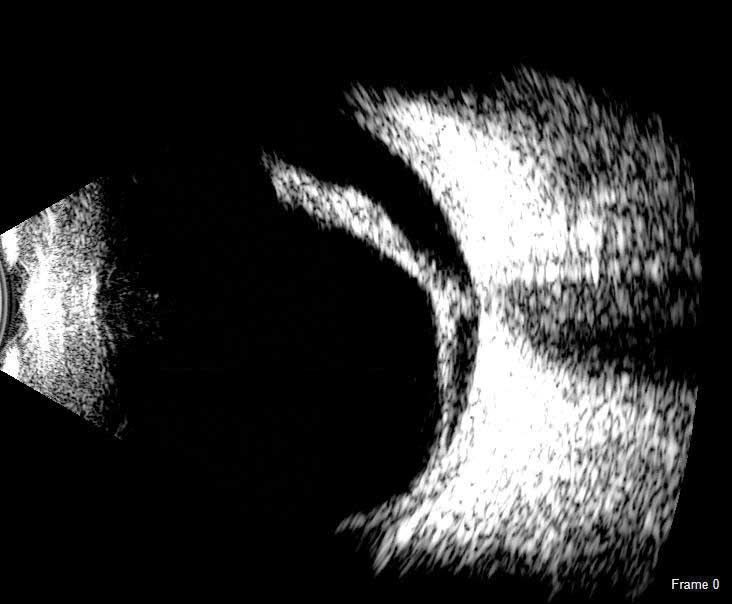

B-Scan

The redesigned B-Scan Probe, new with the Flex, provides clear imaging of the posterior segment of the eye, even when optical clarity is compromised.

The Scanmate Flex B-Scan probe enables clinicians to capture clear and precise images and videos of the posterior segment of the eye. Ultrasonic B-scans are effective, even when opacities (such as dense cataract, blood, or anatomical structures) are present which obscure optical technologies.

The B-Scan probe is available in both 12.5 MHz and 20 MHz frequencies. Among the on-screen tools are calipers to measure structures, an area measurement tool and an annotation tool that gives you a way to indicate pathologies on the image.

B-Scan Diagnostic Applications

The Flex B-Scan delivers clear images of the posterior portion, even when optical clarity is compromised. B-Scan imaging can aid the evaluation of:

- Retinal Detachments

- Vitreous Detachments

- Vitreous Humor Pathologies

- Staphylomas

- Posterior Segment Pathologies

- Choroidal Pathologies

- Optic Nerve Pathologies

- Scleral Thickening